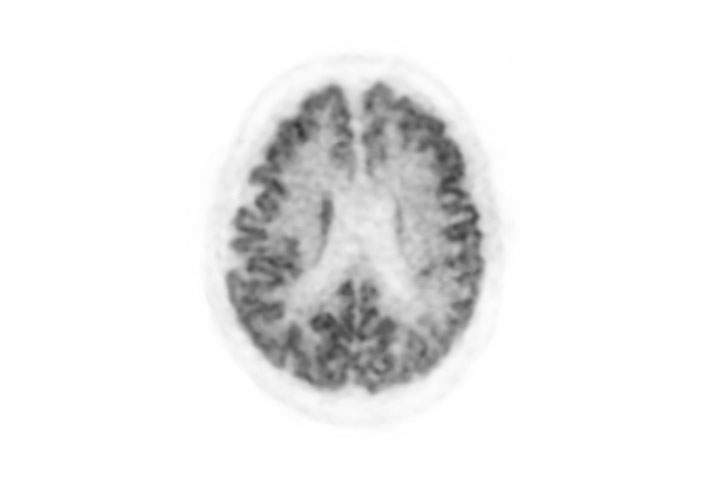

Axial